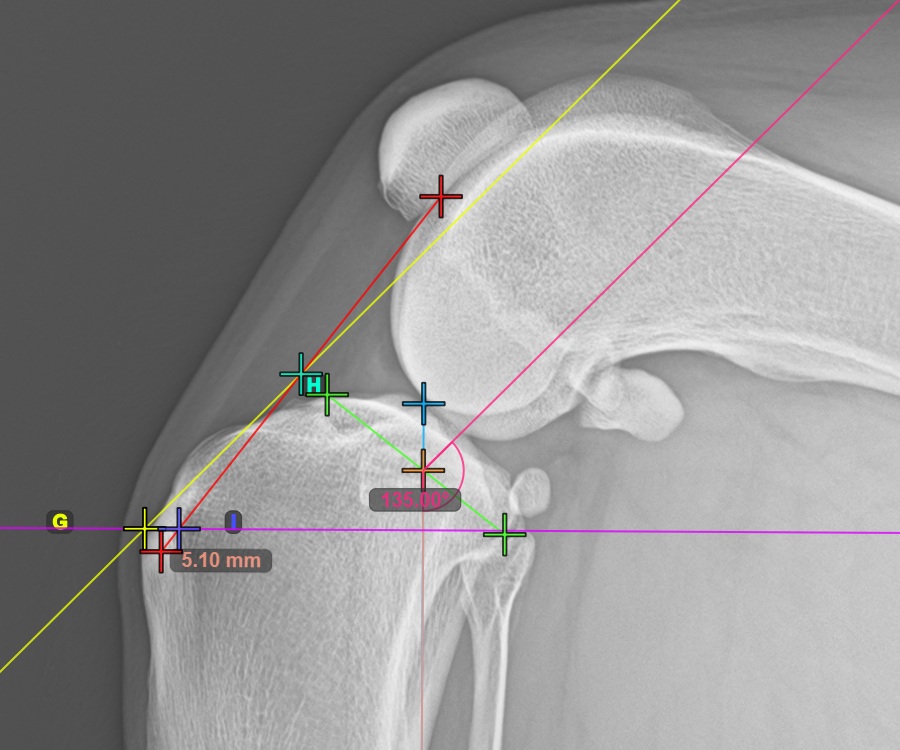

Mark the most caudal point of the tibial head to continue the measurement. Additionally, the software automatically draws a fixed angle measurement of 135°, with the intersection between the long axis of the tibia and the line connecting the most cranial and most caudal point acting as the vertex point for the angle.

The image below depicts the usual placement of the most caudal point on the tibial plateau.

To complete the TTA Rapid variant of TTA measurement procedure mark the most dorsal point of the Crista Tibiae (Tuberositas Tibiae). The distance between the Tuberositas Tibiae and the automatic TTA Rapid helper lines is the required adjustment for the TTA procedure.

The image below depicts the usual placement of the tibial tuberosity, the most prominent point of the tibial crest.